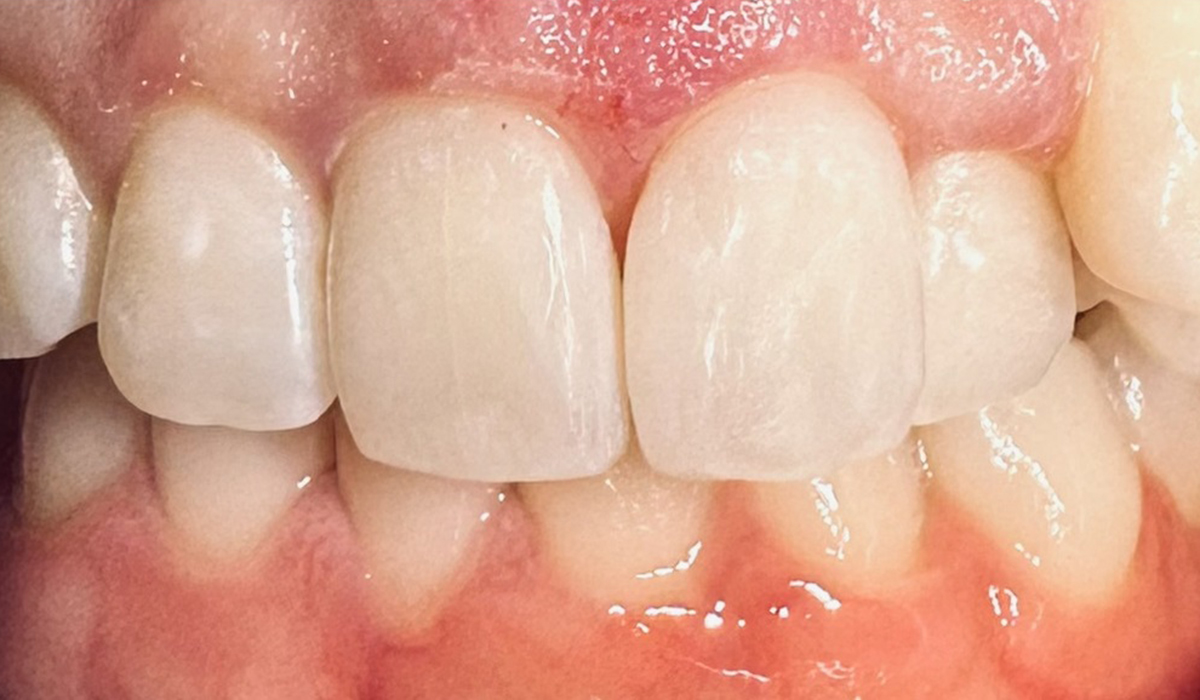

- ブラックトライアングル

ブラックトライアングル(歯と歯、歯ぐきの間にできるトライアングル状のすき間)がダイレクトボンディングで改善された症例です。